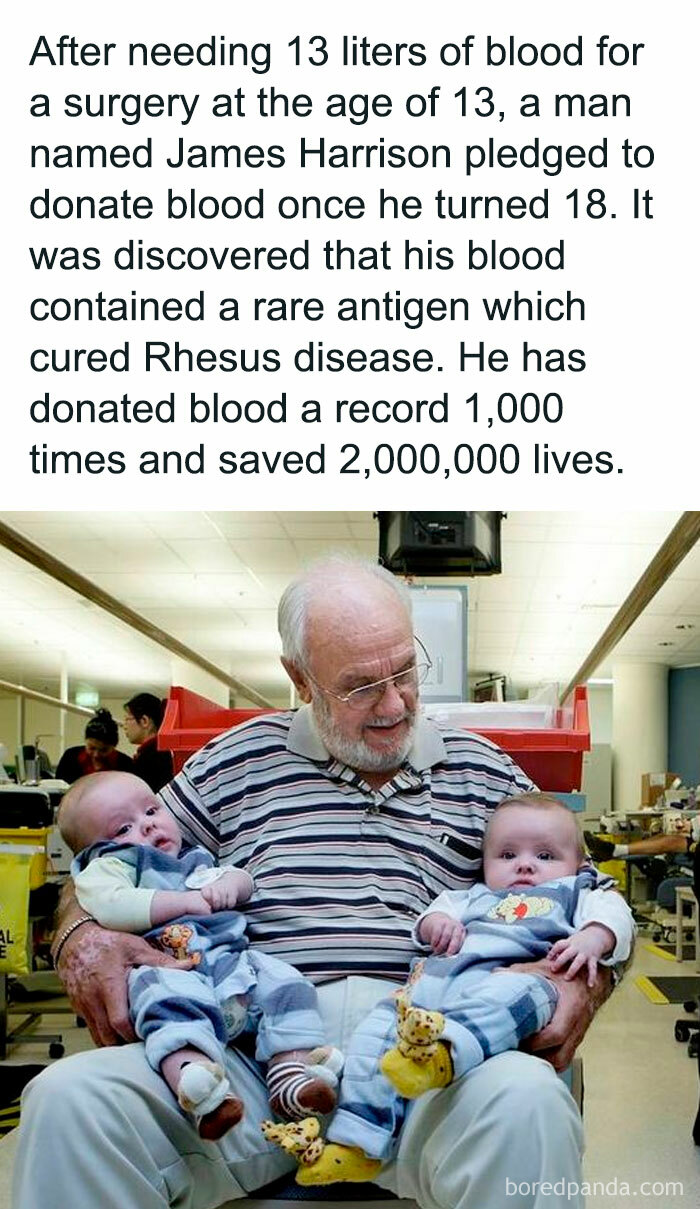

James Harrison The "Man With The Golden Arm"